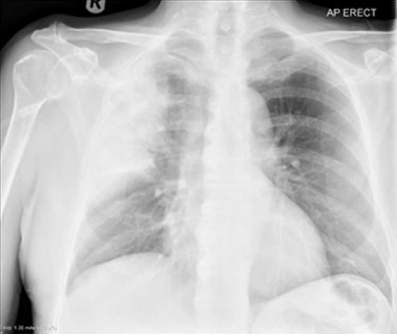

入院时胸片见图1,显示右上肺外周实变。

图1 入院时胸片